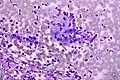

Colorectal adenocarcinoma. Field stain. -